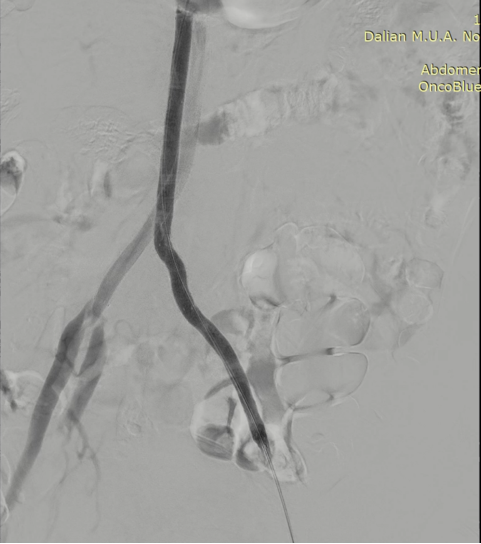

图为:0.018导丝配合pig导管+CXI支持导管翻山,真腔通过

图为:于左髂动脉分叉处依次置入cordis(10-8)接ev3(8-120)支架各1枚,球囊 轻度 后扩

图为:股浅动脉 待二期处理